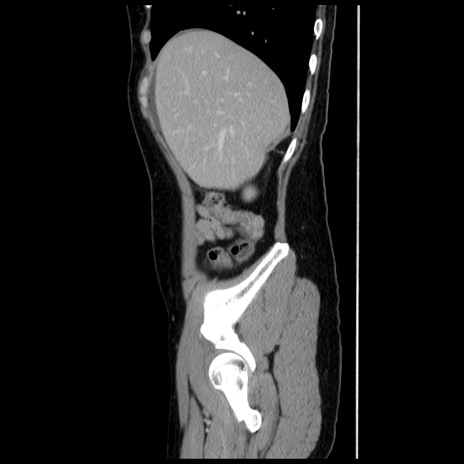

冠状断像

【症例】 50歳代女性

【主訴】 腹痛

【現病歴】前日生レバーを食べた。今朝に排便あり。 昼前に突然発症の腹痛を生じ、当院救急外来を受診した。

【既往歴】 子宮筋腫にてで子宮全摘後

【身体所見】 意識清明、腹部:平坦、軟、下腹部やや左を中心に圧痛・反跳痛あり、筋性防御あり

【データ】WBC 7800、CRP 0.07